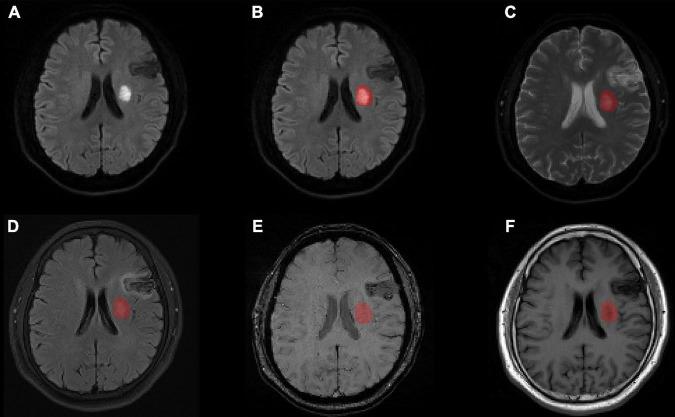

This study retrospectively analyzed 148 patients with acute ischemic stroke due to anterior circulation artery occlusion. Based on the modified Rankin Scale (mRS) score, patients were divided into good (mRS ≤ 2) and poor (mRS > 2) outcome groups. Segmentation of the infarct region was performed by manually outlining a mask of the lesion on diffusion-weighted images (DWI) using MRIcron software. The apparent diffusion coefficient (ADC), fluid decay inversion recoverage (FLAIR), susceptibility weighted imaging (SWI) and T1-weighted (T1w) images were aligned to the DWI images and the radiomic features within the lesion area were extracted for each image modality. The calculations were done using pyradiomics software and a total of 4,744 stroke-related imaging features were automatically calculated. Next, feature selection based on recursive feature elimination was used for each modality and three radiomic features were extracted from each modality plus one feature from the lesion mask, for a total of 16 radiomic features. At last, five machine learning (ML) models were trained and tested to predict stroke prognosis, calculate the received operating characteristic (ROC) curves and other parameters, evaluate the performance of the models and validate their predictive efficacy by five-fold cross-validation.

本研究回顾性分析了148例因前循环动脉闭塞导致的急性缺血性中风患者。根据改良Rankin量表(mRS)评分,将患者分为预后良好(mRS≤2)和预后不良(mRS>2)两组。使用MRIcron软件在扩散加权图像(DWI)上手动勾勒病变掩码,对梗死区域进行分割。将表观扩散系数(ADC)、液体衰减反转恢复序列(FLAIR)、磁敏感加权成像(SWI)和T1加权(T1w)图像与DWI图像对齐,并针对每种图像模态提取病变区域内的放射组学特征。使用pyradiomics软件进行计算,自动计算出总共4744个与中风相关的影像特征。接下来,对每种模态使用基于递归特征消除的特征选择方法,从每种模态中提取三个放射组学特征以及从病变掩码中提取一个特征,共16个放射组学特征。最后,训练并测试了五个机器学习(ML)模型以预测中风预后,计算受试者工作特征(ROC)曲线及其他参数,评估模型性能并通过五折交叉验证验证其预测效能。